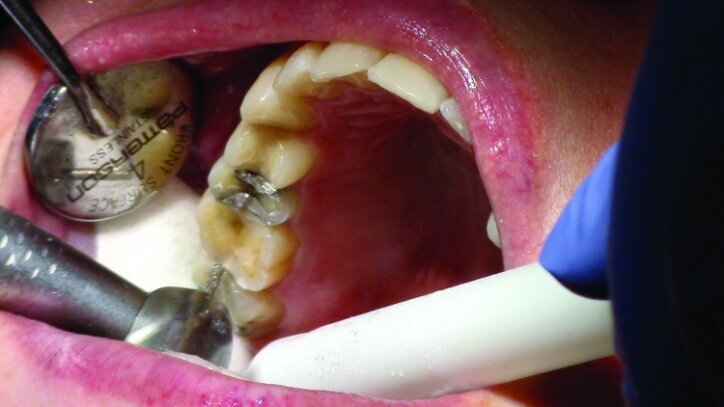

Gross occlusal reduction was completed using a KS7 bur to the depth cuts (Figs. 4–8b, 9c). Adequate clearance was verified with a 2 mm prep check from Common Sense Dental Products.

After gross occlusal reduction was completed, the remaining enamel ring was measured (Figs. 9a, b). The enamel rings were noted to be 1.5 mm, and the teeth were prepared for adhesively retained restorations. If the enamel rings were less than 1 mm, the teeth would have been prepared on the axial walls to create retention for cohesively retained crowns.

The remainder of the existing composite resin in #3 and the amalgam in #4 were removed. The occlusal surfaces of the preparations were blended into the interproximal areas using a KS2 bur to create smooth preparations (Figs. 10–15c). There was no retention or resistance form prepared to retain the restorations.